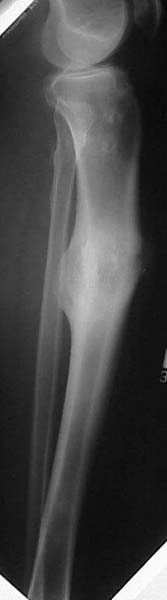

Thanks for the input on the tibia malunion w/ multiple plane deformity. I decided on a single cut osteotomy and IMN fixation based on desire to walk early, return to professor duties, and my previous experience w/ similar deformities (see another tibial malunion -below). The opening wedge was packed w/ a combination of autograft, allograft and demineralized bone.

Another tibial malunion -

Pt was 10 yrs s/p open tibia fx treated in a cast w/ IR, varus, 2 cm short, and recurvatum. He has done well post op.

preop

intraop

18 mos postop